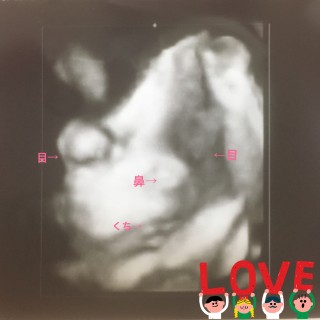

4Dエコーの写真です。このあと必死で顔を隠されました。(笑) すこし顔にへその緒がかかって見えます。